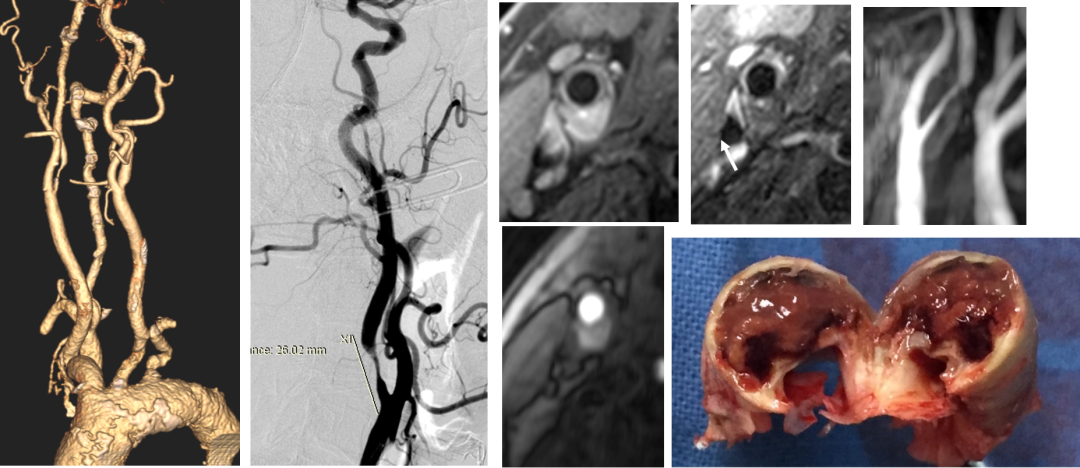

碎屑捕获率:捕获率达到55.88%。这是一个非常震撼的数据。相较于TFCAS术中栓塞保护装置下仍可能发生的“隐形栓塞”,TCAR的逆向血流保护机制能有效将脱落的斑块碎屑逆流引出体外,过滤器内可见肉眼及镜下碎屑,直接证实了其卓越的脑保护效果。

预扩张:85%以上的患者选用5mm及以上直径球囊预扩,最大达7mm。预扩尺寸依据远端正常颈内动脉直径决定,追求一步到位,这与TFCAS中逐级扩张理念有所不同。

双支架置入:本组中有10例患者置入两枚支架。其中2例明确因斑块脱垂导致。这提示对于斑块负荷极重、质地松软的患者,即使有逆向血流保护,支架释放后仍需警惕斑块通过网眼突出。

斑块评估是核心:TCAR围手术期安全性的关键,在于术前对斑块形态学和斑块稳定性的精准判断。一个好的影像评估(斑块负荷、钙化特征、溃疡/血栓)胜过术中万般补救。